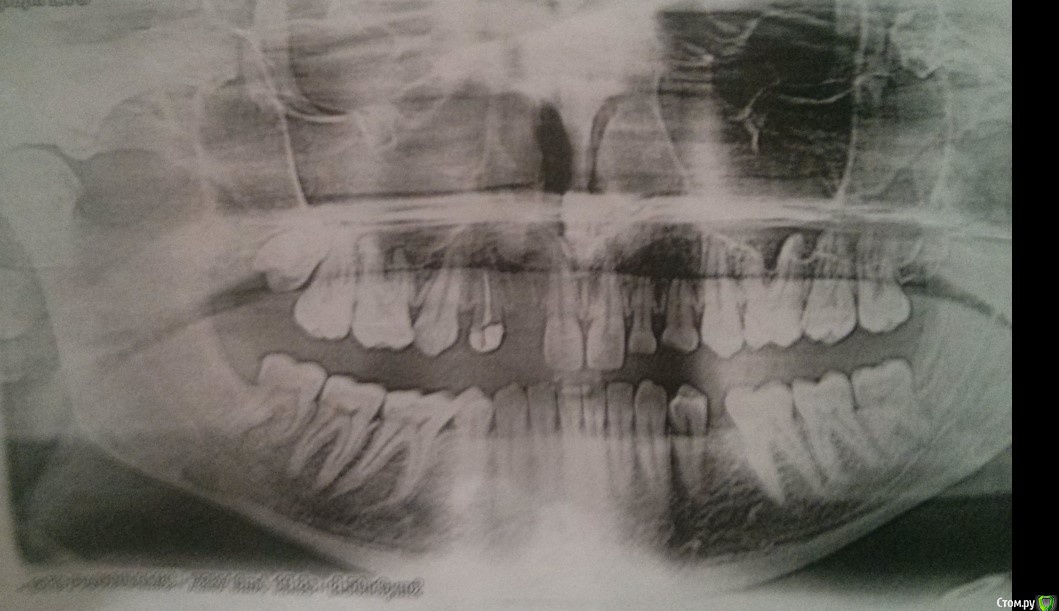

adentiyaHelp Опубликовано 29 марта, 2018 Автор Поделиться Опубликовано 29 марта, 2018 (изменено) Жалобы: проблемы с пережевыванием пищи, нет зуба в переди - как ходить - просто очень комплексую.Провел ортодонтическое лечение на нижней челюсти, поставил 2 импланта. Как протезировать дальше?Снимок 2018, после ортодонтического лечения нижней челюсти: http://prntscr.com/ixzbdh Изменено 29 марта, 2018 пользователем adentiyaHelp Ссылка на комментарий